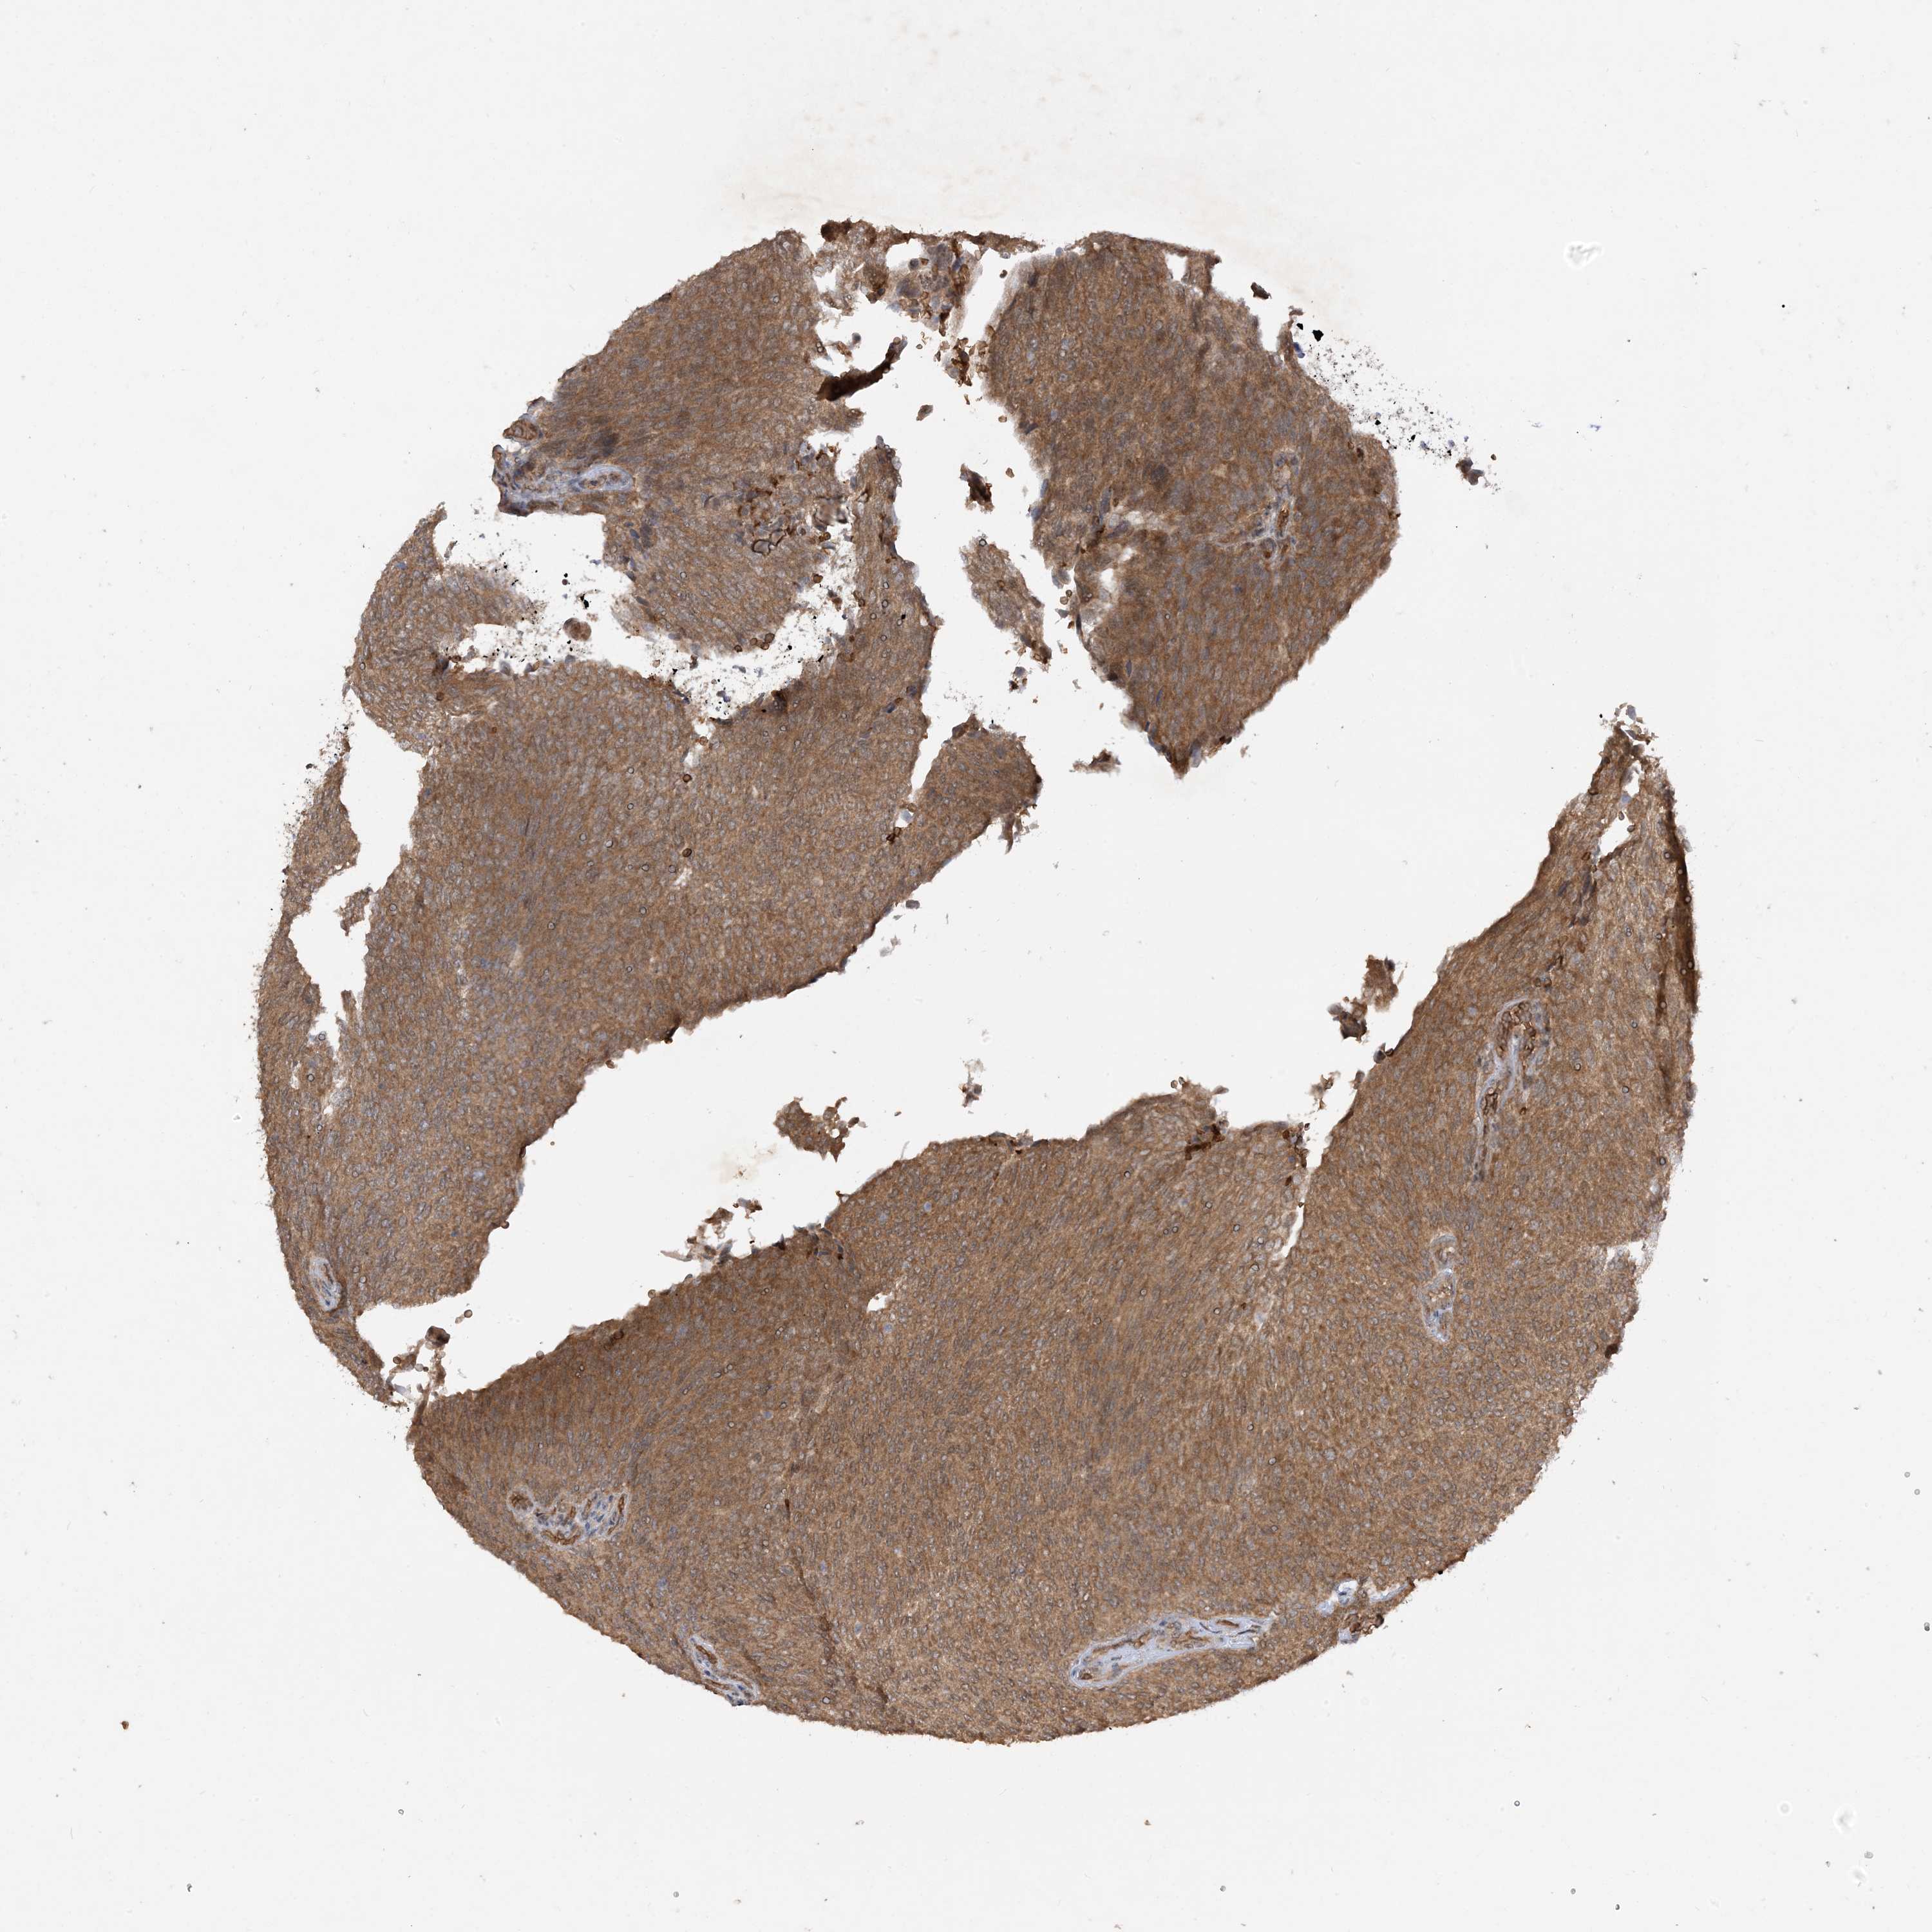

UROTHELIAL CANCER - Protein expressioni

A mouse-over function shows sample information and annotation data. Click on an image to view it in a full screen mode. Samples can be filtered based on level of antibody staining by selecting one or several of the following categories: high, medium, low and not detected. The assay and annotation is described here.

Note that samples used for immunohistochemistry by the Human Protein Atlas do not correspond to samples in the TCGA dataset.

Antibody stainingi

Antibody staining in the annotated cell types in the current human tissue is reported as not detected, low, medium, or high, based on conventional immunohistochemistry profiling in selected tissues. This score is based on the combination of the staining intensity and fraction of stained cells.

Each image is clickable and will lead to virtual microscopy that enables deeper exploration of all samples and also displays staining intensity scores, fraction scores and subcellular localization as well as patient and tissue information for each sample.

Antibody HPA032057

Staining

High

Medium

Low

Not detected

Intensity

Strong

Moderate

Weak

Negative

Quantity

>75%

75%-25%

<25%

None

Location

Nuclear

Cytoplasmic/membranous

Cytoplasmic/membranous,nuclear

Urothelial carcinoma, Low grade

Urothelial carcinoma, High grade